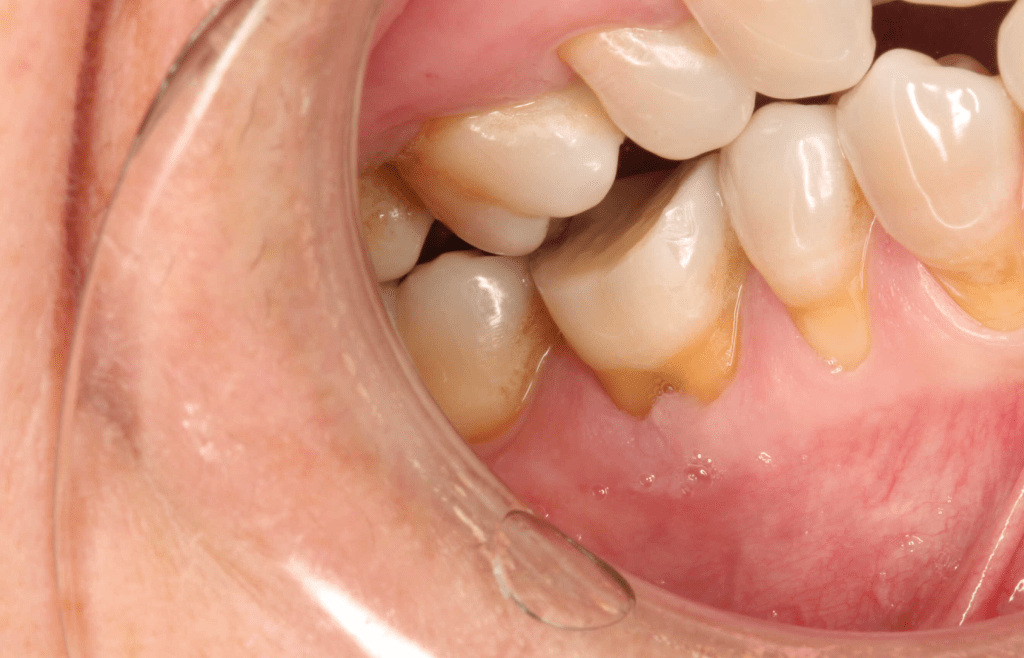

Reco pared vesticular